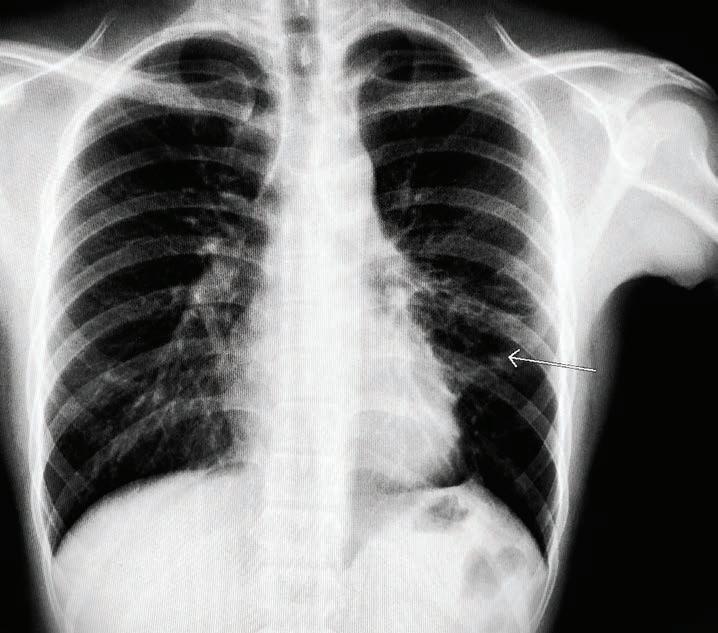

UHN-created tool that supports Emergency Department (ED) physicians in deciding whether to admit or discharge a heart failure patient is now available in Epic, UHN’s electronic patient record system.

The Emergency Heart Failure Mortality Risk Grade (EHMRG) calculator estimates the risk of a heart failure patient dying within one week, and over the course 30 days, based on 13 key metrics calculated in the ED.

Based on the score, different courses of action are recommended depending on a patient’s risk category.

The Epic integration at UHN is the first in Canada for this decision-support tool.

The EHMRG calculator, which was created by Dr. Douglas Lee, a cardiologist at UHN’s Peter Munk Cardiac Centre where he is Ted Rogers Chair in Heart Failure Outcomes, was validated in a clinical trial –“Comparison of Outcomes and Access to Care for Heart Failure (COACH)” – at 10 hospitals across Ontario. The results were in a study published in the New England Journal of Medicine in 2023.

The EMHRG calculator provides a low-risk, intermediate-risk, or highrisk score based on the patient’s presenting metrics at the ED, such as age, blood pressure, creatinine and potassium levels, and whether they arrived by ambulance.

Low-risk patients can be safely discharged from the hospital and given a follow-up appointment with a heart function clinic within two weeks. High-risk individuals should be admitted from the ED for immediate care and ongoing monitoring.

An intermediate-risk score prompts further consultations with hospital specialists to determine if the patient can be discharged with a follow-up appointment within a few days, or should be admitted for monitoring.

It supports clinical decision-making with an objective and evidence-based score – generated automatically and quickly – to help ensure the safety of patients and efficiency of the workflow in a busy ED. This improves patient quality of life, ensures allocation of hospital resources to those in most critical need and reduces health care expenses.

“In the fast-paced environment of Emergency Departments, where decisions can mean the difference between life and death, the Emergency Heart Failure Mortality Risk Grade (EHMRG) score provides timely insights to help make the right decision,” says Dr. Lee, whose work on the project was funded by the Ted Rogers Centre for Heart Research and Institute for Clinical and Evaluative Sciences (ICES).

“Heart failure is complex, and objective measures like the EHM-

RG score can complement physician clinical judgment.”

Before receiving the greenlight for integration into Epic, the EHMRG calculator was first validated in the COACH trial.

The trial at 10 Ontario hospitals saw more than 5,000 patients who came into the ED with acute heart failure divided into two groups. One received usual care, and the other received a special hospital-based strategy using the EHMRG calculator to help physicians determine which patients were able to be safely discharged with follow-up.

The results showed that within 30 days of receiving treatment, the group using the EHMRG calculator had a lower rate of either dying from any cause or being hospitalized again for heart problems compared to the group that received usual care. Over 20 months, the difference in health outcomes between the two groups continued to be better for the EHMRG care group.

Specifically, only the patients in the EHMRG calculator group experienced a statistically significant reduction in death or repeat hospitalization for cardiovascular reasons compared to the control group.

The study concluded that for patients with acute heart failure, receiving care informed by their individual risk level determined with the EHMRG calculator score in tandem with rapid follow-up at a heart function clinic resulted in a lower risk of mortality or re-hospitalization.

It was this promising result that led the Epic and UHN teams to design an integrated care pathway for the ED that incorporated the EHMRG calculator score and integrated it into Epic at multiple UHN sites.

This is the latest tool from the Ted Rogers Centre for Heart Research to be integrated for widescale use across Ontario hospitals, showcasing the incredible impact of both the research and translational work being done by its scientists and clinicians.

“By integrating this calculator into the Epic system at UHN, we’re not just enhancing the decision-making process, we’re helping to transform the way heart failure is managed in the Emergency Department,” says Dr. Lee. “It’s a step forward in our mission to improve the quality of care for heart failure patients across the province.” ■ H